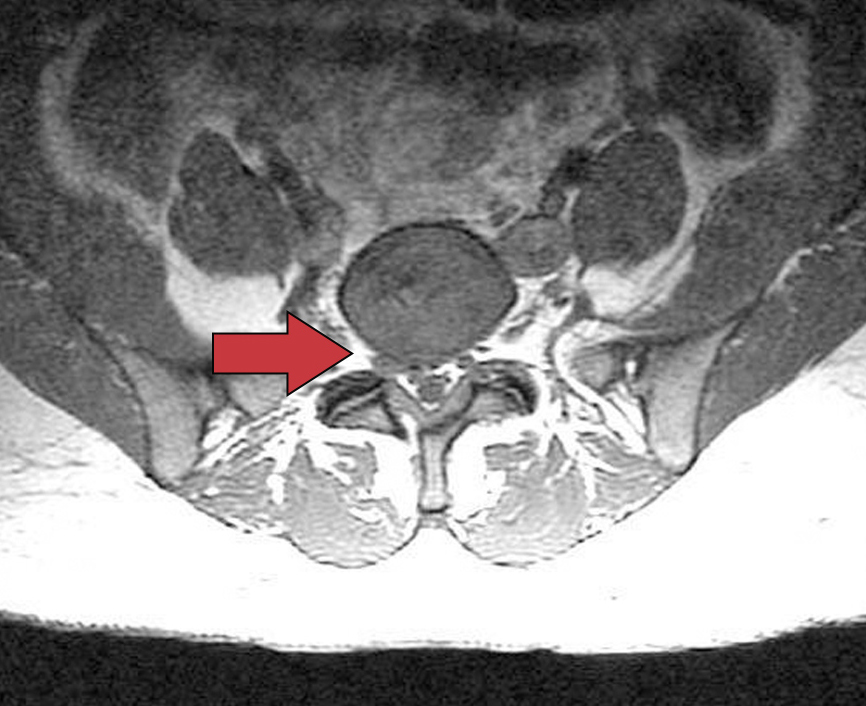

上述所有选项都是导致臀中肌步态(鸭步),但只有腰椎神经根病能够解释患者发作的时间和疼痛症状。腰骶神经根病发生在约3%~5%的人群中,男女患病比例相似,40余岁的男性和50余岁的女性最容易患此类疾病。患有这种病症的患者中有10%至25%发生持续6周以上的症状。上图显示的是临近右侧L5神经根旁的腰椎间盘突出

。